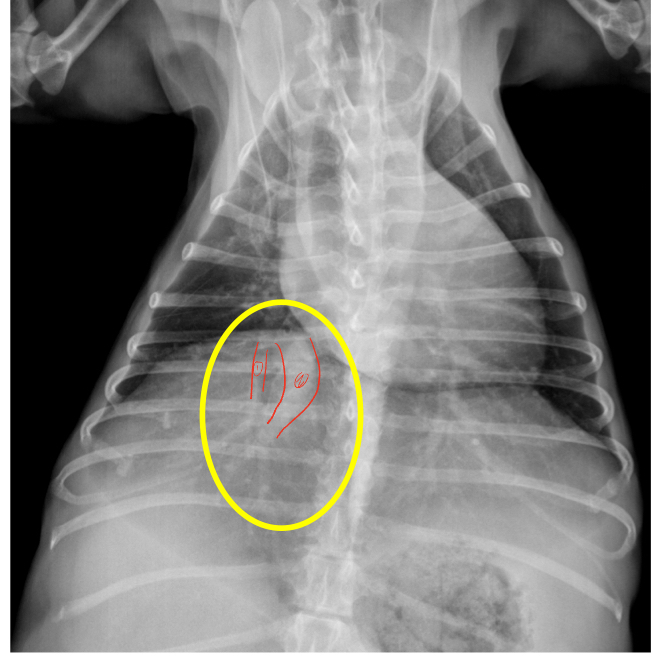

1 month old leonberger presented with distress and lethargy. What wrong

peritoneal-pericardial diaphragmatic hernia